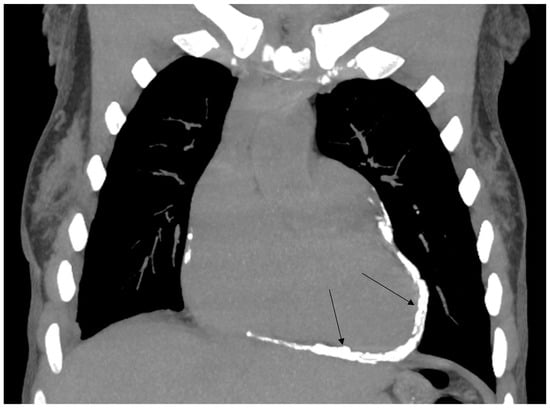

Cardiac Post-Chest Radiotherapy Complications in a 50-Year-Old Patient with Hodgkin Lymphoma

2. Case Report